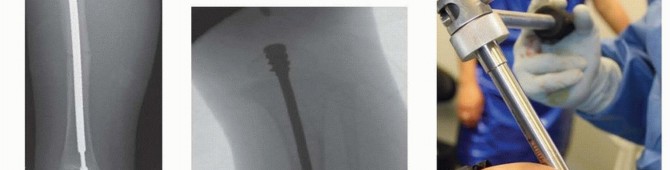

## The keys to surgical success are careful selection of children with adequate bone strength, size, and availability of an experienced team and appropriate equipment (FIG 4A).

## Templates must be used to ensure that every appropriate size and type of device is available (FIG 4B).

## Radiographs can be used to estimate length and diameter of nails as well as to determine osteotomy sites (FIG 5).

## Measuring the Fassier-Duval nail

The distance from the greater trochanter to the distal femoral physis can be used to estimate the length of the female nail.

## The female nail should be approximately 1 cm shorter than this distance.

Digital software and templates to determine length and diameter of the nails are available.

The long-threaded female nail is used in the femur and does not require a knee arthrotomy for placement. The “small bone” shorter threaded female nail does not require an ankle arthrotomy for insertion into the tibia and can also be used in the humerus.

FIG 4 • A. Fassier-Duval nail insertion tray. B. Templates for Fassier-Duval nail. (B: Courtesy of Pega Medical, Inc., Montreal, Canada.)